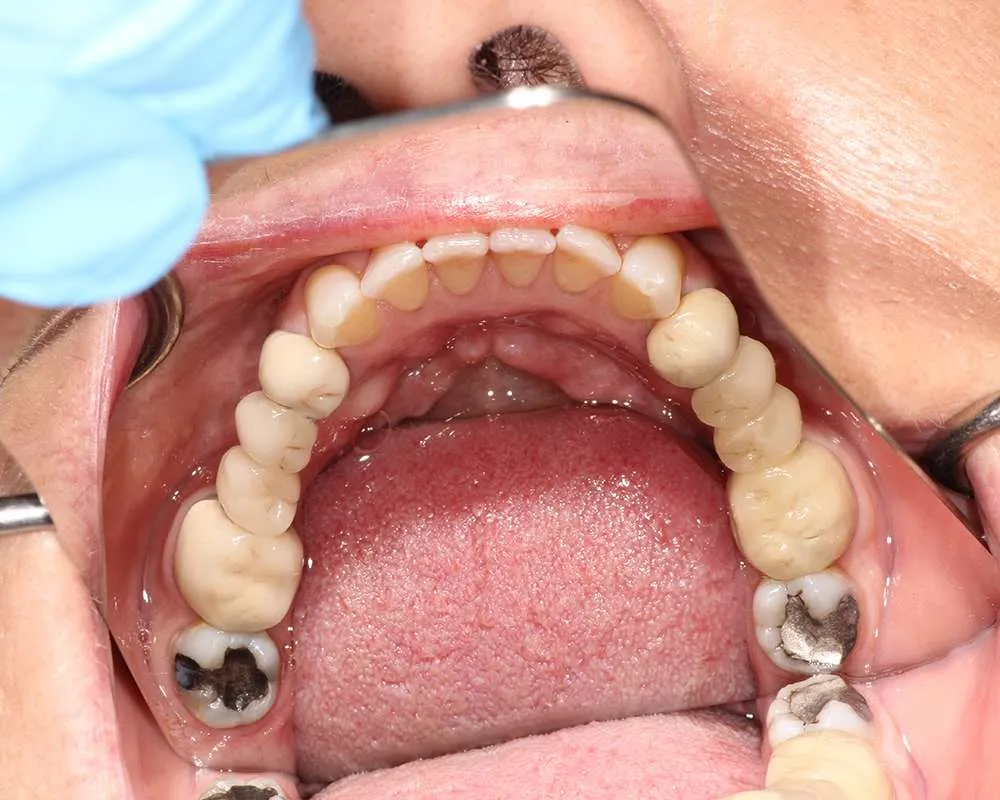

The safe removal of mercury fillings is crucial for your health and well-being. At our practice, we follow strict protocols to ensure that mercury amalgam fillings are removed safely and effectively.

Amalgam fillings removed